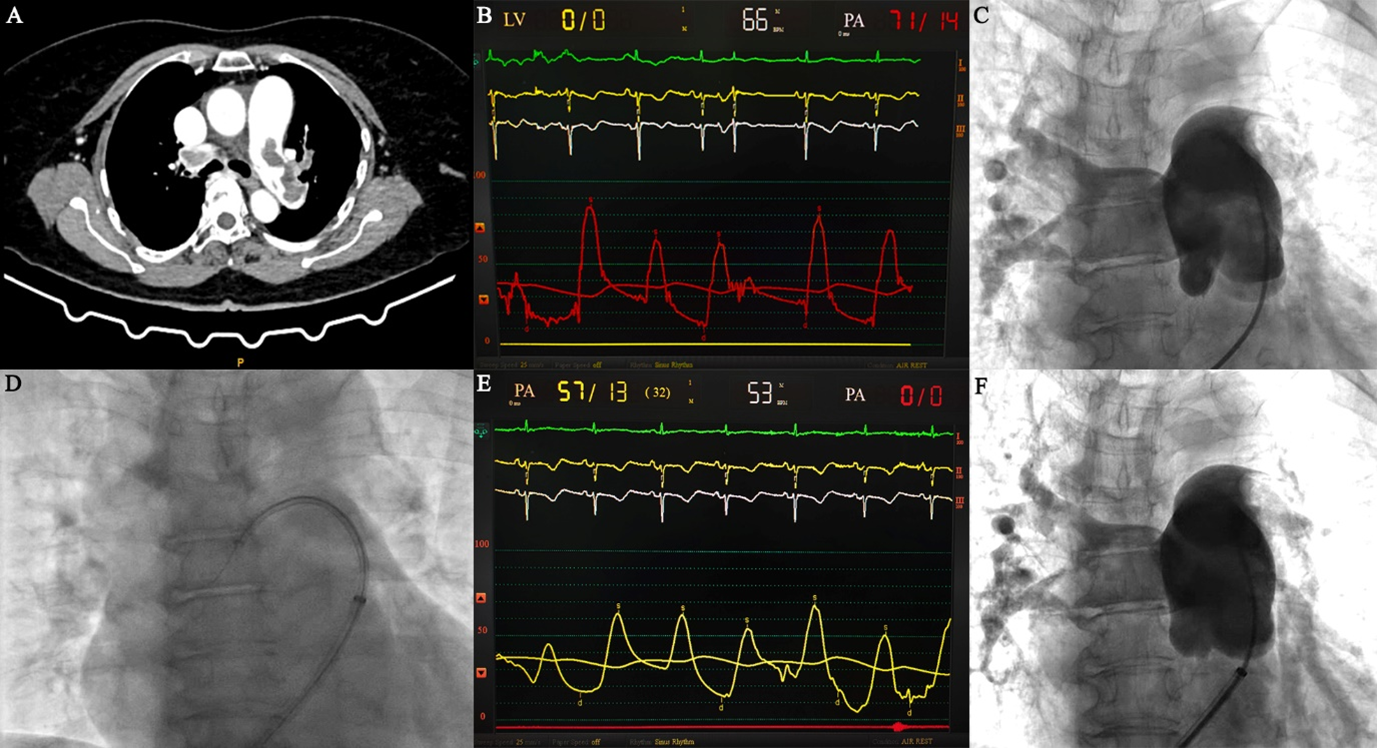

Repeat CT was done to look for resolution of the pulmonary thrombus. However, persistent pulmonary artery thrombus was noted (Figure 2A) and a percutaneous aspiration thrombectomy was planned. The pulmonary artery systolic pressure (PASP) was 71 mm Hg (Figure 2B) and a pulmonary angiogram showed a dense filling defect in the main and right pulmonary arteries (Figure 2C, Video 3). An 80-cm 10-French Flexor sheath (Cook Medical) was taken into the right pulmonary artery over a 0.035-inch Teflon wire. Multiple runs of thrombus aspiration were done with an Indigo system CAT 8 aspiration catheter (Penumbra) in the main, right upper, right lower, and left pulmonary arteries (Figure 2D). A 0.035-inch J-tip separator wire (Terumo) was passed through the thrombus to break it to facilitate suction. The PASP reduced to 57 mm Hg (Figure 2E) and pulmonary angiography showed minimal resolution of the filling defect after thrombo-suction (Figure 2F, Video 4).